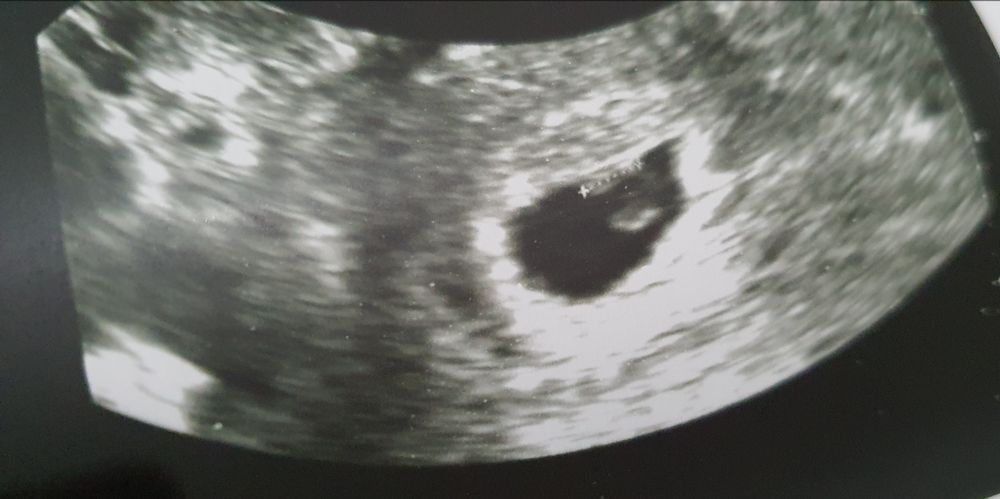

Добрый вечер. Сколько эмбрионов на снимке узи вы видите, срок 6 недель? Врач узи внятный ответ дать не смог, в заключении тоже не указал точное количество, написала 1 эмбрион, но на словах сказала, что не уверена в количестве. Вот покоя же нет теперь, до следующего узи 7 дней, сердечко будут слушать, изведусь ведь вся. А вам сколько кажется?

Один и ЖМ вижу

Чудесно если так, у нас пятеро детей, и сразу к двум не готова. А врач узист сегодня крутила-вертела, сказала что не уверена что один. То-ли врач такой, то-ли что.